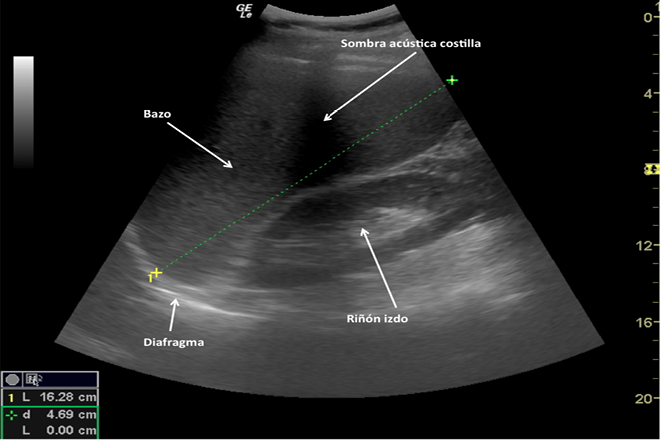

Esplenomegalia

La esplenomegalia se refiere al aumento del tamaño del bazo, que en un adulto tiene unas dimensiones aproximadas de 12 × 7 × 3.5 cm, un peso de 150 g y un volumen de 300 ml. Este órgano desempeña un papel fundamental en la respuesta inmune, actuando como un filtro sanguíneo para eliminar los glóbulos rojos envejecidos, así como otras células sanguíneas unidas a anticuerpos. En la pulpa roja esplénica se destruyen los glóbulos rojos envejecidos y se eliminan las inclusiones celulares de los reticulocitos. Por otro lado, la pulpa blanca contiene macrófagos y linfocitos B y T que participan en la detección de microorganismos y proteínas extrañas como parte de la respuesta inmune primaria, siendo el bazo el principal productor de IgM, especialmente durante la infancia.